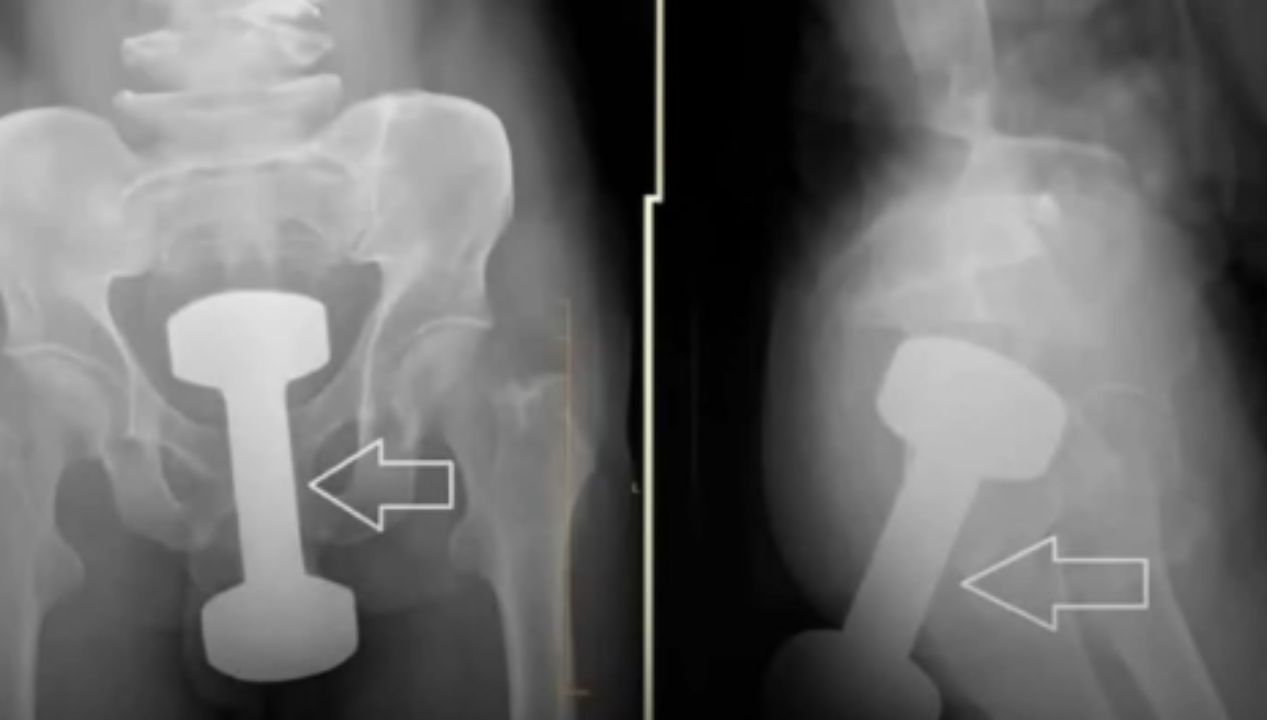

एका व्यक्तीने रेडिटवर दोन फोटोंसह एक पोस्ट शेअर केली. त्या माणसाने सांगितले की हे दोन्ही फोटो त्याच्या स्थानिक डॉक्टरांनी शेअर केले आहेत. तथापि, या फोटोंमध्ये जे दिसत आहे ते खूपच धक्कादायक आहे. हे फोटो एका माणसाचा एक्स-रे आहेत, ज्यामध्ये त्याच्या शरीरात एक मोठा डंबेल असल्याचे दिसून येते. त्या माणसाच्या शरीरावर डंबेलसारखी वस्तू असल्याचे पाहून डॉक्टरही थक्क झाले. तथापि, व्यक्तीची नंतर शस्त्रक्रिया करण्यात आली, त्यानंतर त्याच्या शरीरातून जे बाहेर पडलं ते खरोखरच धक्कादायक होत. माणसाच्या शरीरातून चक्क २.५ किलो वजनाचा डंबेल बाहेर काढण्यात आला. माहितीनुसार, जेव्हा डॉक्टरांनी त्याला इतका मोठा डंबेल शरीराच्या आत गेला कसा याविषयी विचारलं तेव्हा व्यक्तीने कोणतेही उत्तर देण्यात नकार दिला. रुग्णाला स्वतःच हे सांगता आले नाही की इतका मोठा डंबेल त्याच्या शरीरात कसा आला.